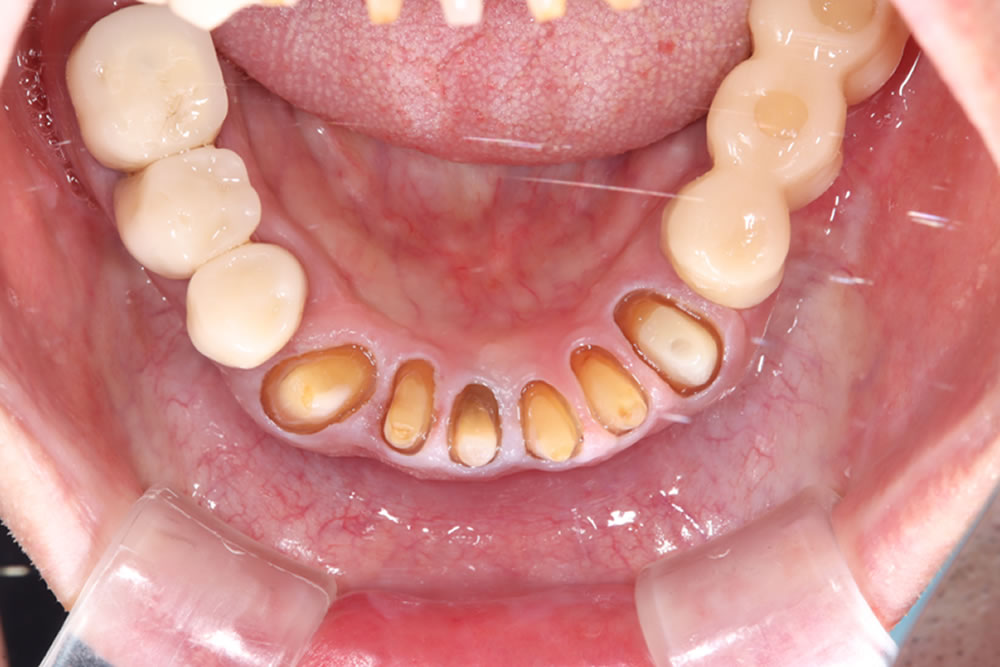

こちらの患者さまは、上の歯が抜けそうとの主訴で来院されました。上顎ブリッジが大きく動揺している状態、下の歯は動揺はありませんでしたが、全体的に虫歯や歯石の沈着が確認できました。

レントゲン検査

レントゲン精査を実施。上顎残存歯は歯を支える骨がほとんどなくなっており、保存するのは不可能な状態(重度歯周炎)と診断しました。

抜歯・即時義歯の装着

まずは応急的に咬み合わせを回復するため、保存不可能と診断した上顎歯の抜歯を行い、同時に即日義歯を装着しました。

今後の治療方針として、下顎の欠損部にはインプラント治療を行い、残存歯については補綴治療を実施することとなりました。